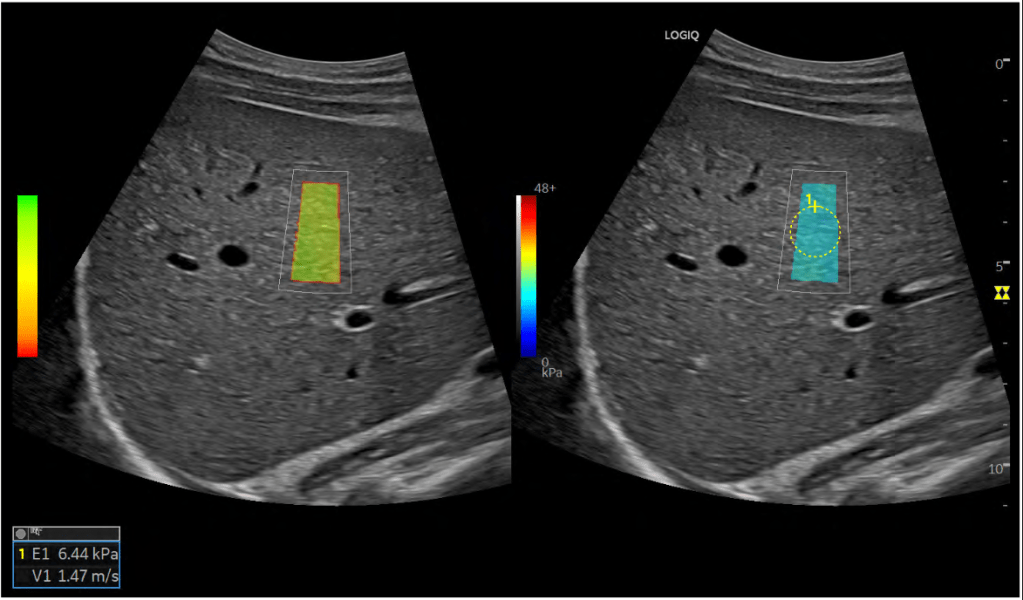

Durante a evolução do fígado de F0 (sem fibrose) até F4 (cirrose), as cicatrizes tornam órgão cada vez mais endurecido, ou menos “elástico”. Como consequência, se você aplicar uma força, ela se propaga pelo fígado com maior ou menor dificuldade dependendo de quão “sólido” o fígado está.

O primeiro método comercialmente bem sucedido para explorar essa característica da fibrose hepática foi o Fibroscan, um aparelho semelhante a um ultrassom desenhado exclusivamente para realizar a elastografia. Ele age aplicando uma vibração no fígado e medindo a consequência dessa no órgão. Assim que surgiu todos os centros de pesquisa de hepatologia correram para pesquisar o seu uso e comprovaram que o método é confiável para esclarecer o grau de fibrose, mas não permite avaliar a estrutura do fígado, fica mais impreciso em pacientes obesos e não funciona em pacientes com ascite. Além disso, o aparelho e sua manutenção são muito caros, o que se reflete no alto custo do exame.

Uma vez definido que a elastografia era confiável e começou a ser integrada na prática clínica, chegou a vez dos aparelhos convencionais de ultrassom alcançarem (e ultrapassarem) o Fibroscan.

A ultrassonografia ARFI Point Shear Wave (pSWE), ou sua evolução, a 2D Shear Wave (2D-SWE), diagnostica a fibrose com alta precisão: comparando com a biópsia hepática, tem acerto de 87% para fibrose F2, 91% para F3 e 93% para cirrose (F4). Vale a pena destacar que nem sempre a biópsia é perfeita: trata-se de um pedacinho muito pequeno do fígado que pode ter uma doença que não se apresenta de forma igual e todo o órgão. Na biópsia, estima-se que seja analisado 1/50.000 do fígado, enquanto que na elastografia onde você avalia uma área, essa pode corresponder a 1?500 do fígado, uma parcela bem mais representativa.

Outras vantagens da elastografia por ultrassom é que mantém a precisão mesmo em pacientes obesos, como você seleciona a região da análise ela não é prejudicada por ascite. Além disso, como é um aparelho de ultrassom, você também pode avaliar toda a estrutura do fígado e diagnosticar outros problemas, como trombose ou câncer.